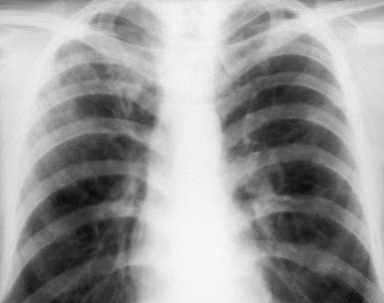

Рис. 2 Очаговый туберкулез легких в фазе петрификации